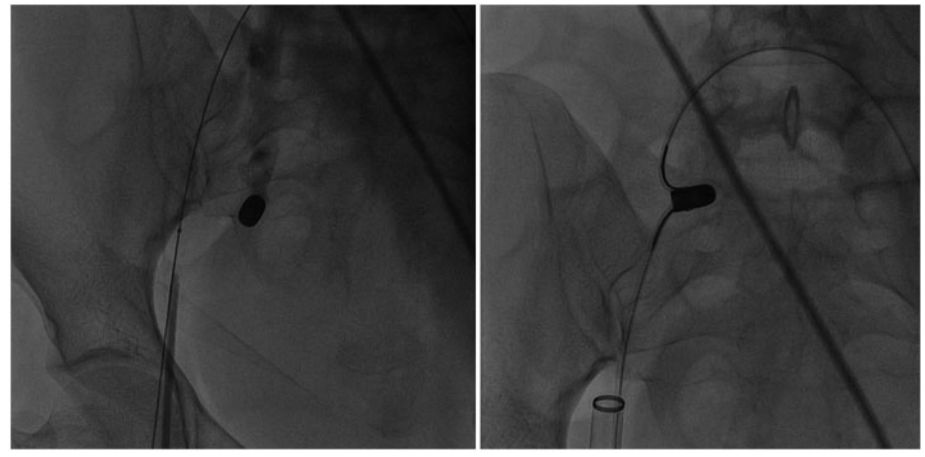

之后,*弹子**滑出向上移动到髂总静脉,并向下移动至右侧髂内静脉,如图4左。为了避免*弹子**滑脱,应在腹股沟*弹子**附近画一8字形缝合线。之后,选择由24-Fr鞘、JR 5-Fr引导管和15 mm的鹅颈管圈套组成的组件通过右侧股静脉,并在右侧股静脉内处理鹅颈管套圈。同时使用两个套圈捕捉*弹子**(图4右侧),并通过24-Fr鞘将*弹子**在右股静脉内安全取出,最终使用8号缝合线缝合静脉。

图4 左:*弹子**在套圈中滑脱,向上移动至右侧髂总静脉,之后又向下移动至右侧髂内静脉;右:两个股静脉套圈均捕获*弹子**

手术后,没有任何心律失常,取出的*弹子**(长12 mm,宽6 mm),如图5右所示。

图5 左:将*弹子**从右股静脉的24-Fr鞘中取出;右:取出套圈中的*弹子**(长12 mm,宽6 mm)